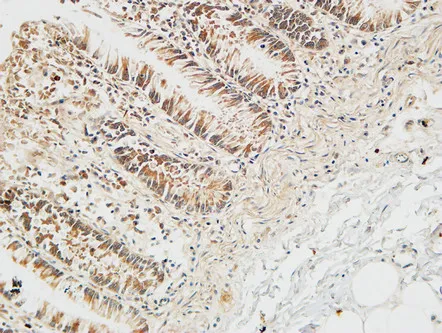

MCP-3 Rabbit Polyclonal Antibody

Cat: APRab13734